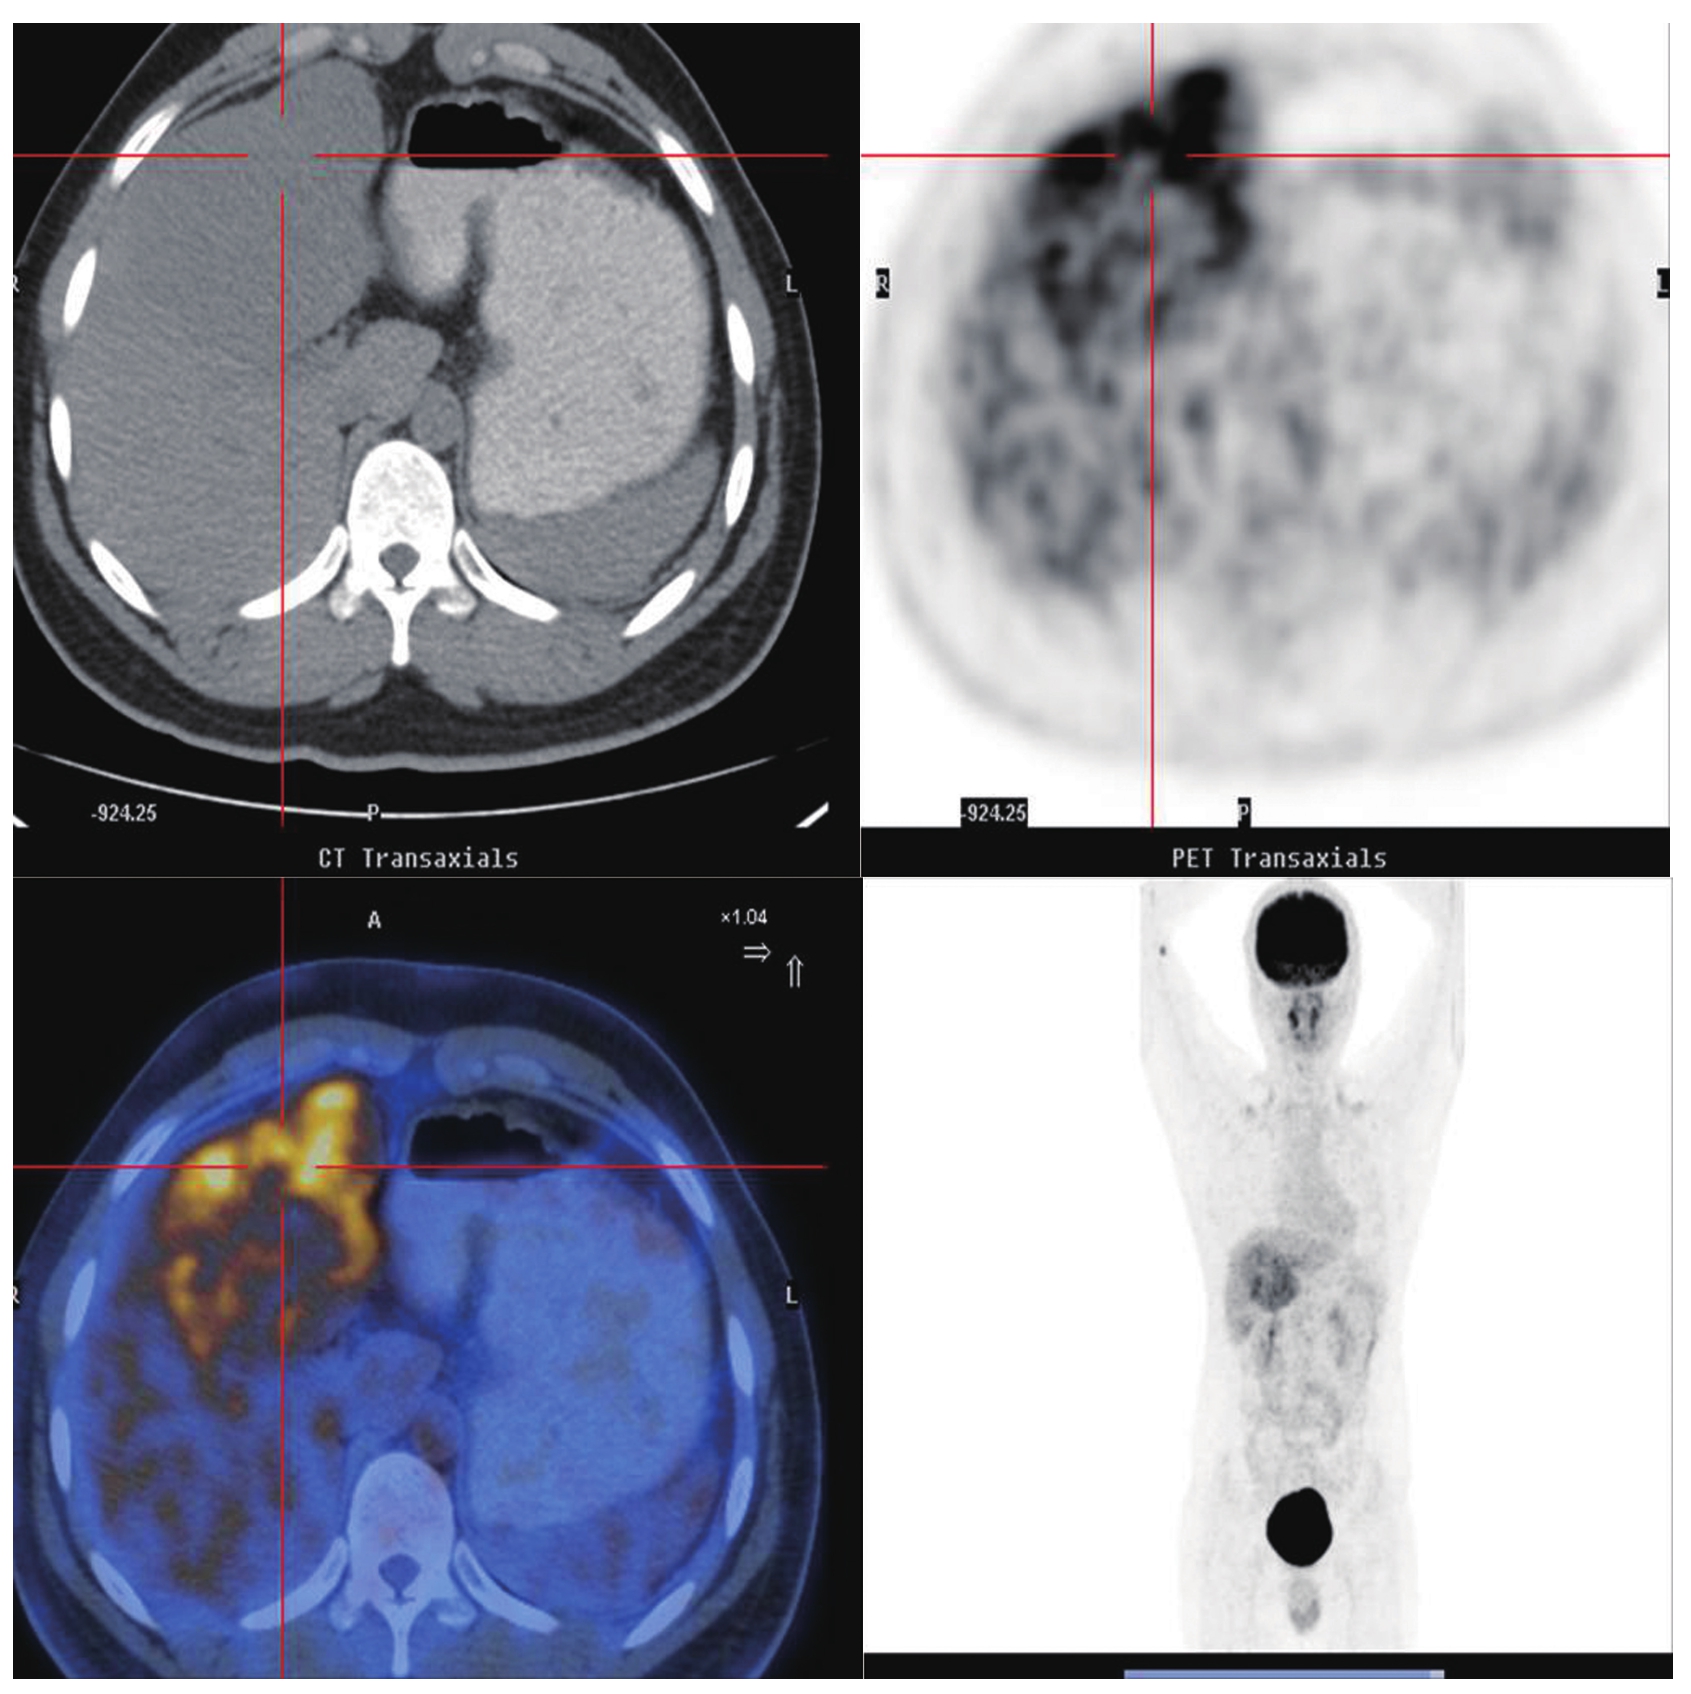

图5-21-39 HCC患者的 18 F-FDG PET/CT图像

肝左、右叶团块状、结节状稍低密度影,边缘尚清,较大者大小约10.7cm×8.8cm,CT值约45HU,PET显像见异常放射性浓聚,SUV max 7.1